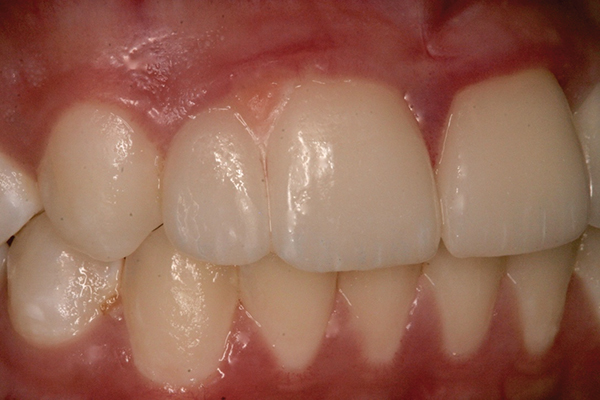

Fig 13 to Fig 16. Post-treatment photographs.

When the patient was 19 years old, the lithium-disilicate veneers and the ceramic crown were tried in and evaluated. Following modification, the veneers were carefully cemented with an adhesive resin cement following application of silane to the intaglio surfaces, etch of the enamel, and application of primer and adhesive. The intaglio surface of the implant crown was treated with a porcelain etch product and silane, and the crown was cemented with carboxylate luting cement with 1 drop of water for retrievability. A paintbrush was used to apply a thin layer of cement to minimize excess. Any excess cement on the veneers and crown was meticulously removed, and the margins and occlusion were carefully checked. The patient returned 2 weeks later (Figure 13 through Figure 18) for a review of her oral hygiene and for fabrication of a nightguard. The patient was happy with the esthetic result and exclaimed she had been stopped on the street and told she had a beautiful smile.